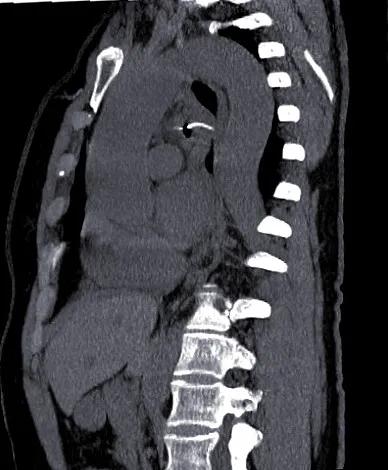

CT重建

急诊科医生仔细查看CT,发现鱼刺处于食管第二狭窄下端,并已经穿透食管壁、纵隔、穿入左主支气管内!

对照外院CT,鱼刺有移动趋势。